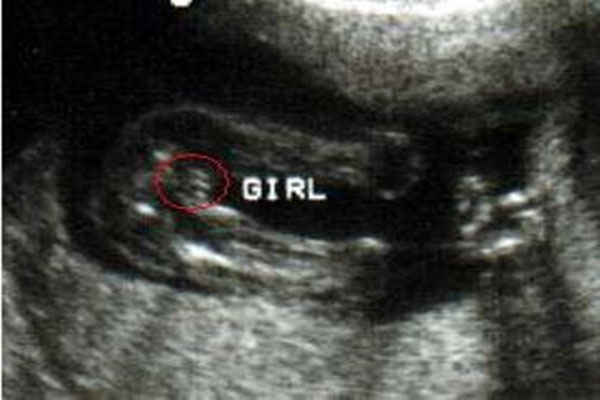

孕26周四维下睾丸的样子 如何看四维彩超识性别呢?

四维彩超,相信很多妈妈都是熟悉的,特别是孕妈妈们都是做过四维彩超的,它与普通B超不同,是非常先进的排畸仪器设备。好友珊珊怀孕刚好26周,前些日子陪着一起去做四维彩..

从b超单上如何看性别 儿女双全妈妈经验总结

从b超单上如何看性别 做B超检查的时候,许多孕妈妈都想知道腹中胎儿的性别,这并不是重男轻女思想的禁固,完全是个人的好奇心作怪。孕妇肚子里是男孩还是女孩,这是让很多..

nt检查如何看男女?通过nub点看男女准确率高吗?

nt检查如何看男女?通过nub点看男女准确率高吗?nub又叫nubtheory,指的是胎儿的生殖节,nub最早出现在英国,因为很多人都认为nub可以准确的判断出胎儿的性别,所以在母亲..